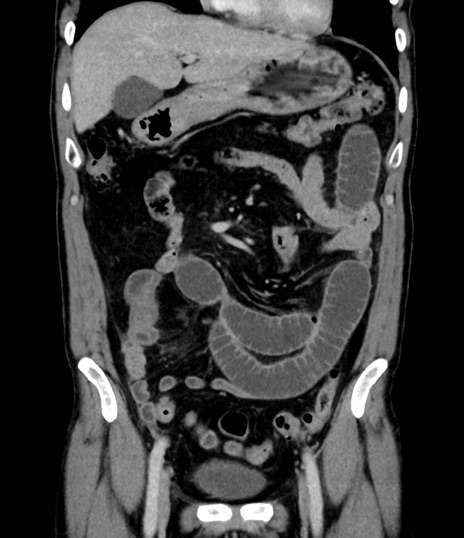

症例8(冠状断像)

【症例】 60歳代男性

【主訴】 黒色吐物

【現病歴】 4日前から嘔気自覚、2日前の朝食後にも嘔気あり、自分で手で嘔吐反射起こし嘔吐したところ血が混ざっていたため受診。

【既往歴】 5年前汎発性腹膜炎を伴う急性虫垂炎で手術、高血圧、前立腺肥大症、高脂血症

【身体所見】 腹部正中に手術癩痕あり 腹部平坦・軟圧痛なし膨満感あり

【データ】WBC 8400、CRP 4.54